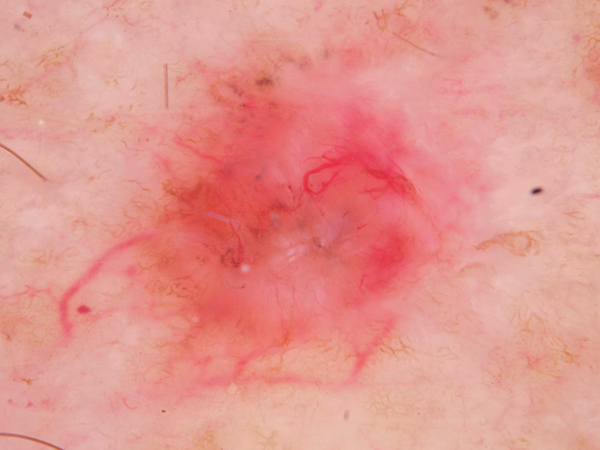

Basal cell carcinoma